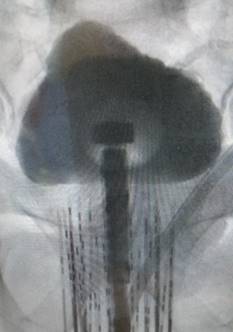

Fluoroscopic image of needles containing radioactive elements placed into the prostate according to the physics plan. |

Using needles passed through the skin behind the scrotum, radioactive elements (or “seeds”) are permanently placed (or implanted) directly into the prostate where they give off low-level radiation continuously for 3 to 8 months, depending on type. Using trans-rectal ultrasound guidance, these seeds can be positioned so that the radiation is distributed accurately throughout the prostate gland and surrounding margin according to a unique physics plan developed for each individual patient. Since only a small area is irradiated by each seed, relatively little radiation reaches the adjacent normal organs such as the rectum or bladder. For this reason, the total dose of radiation delivered to the prostate is 2 to 4 times that which can be delivered by external beam therapy or IMRT.